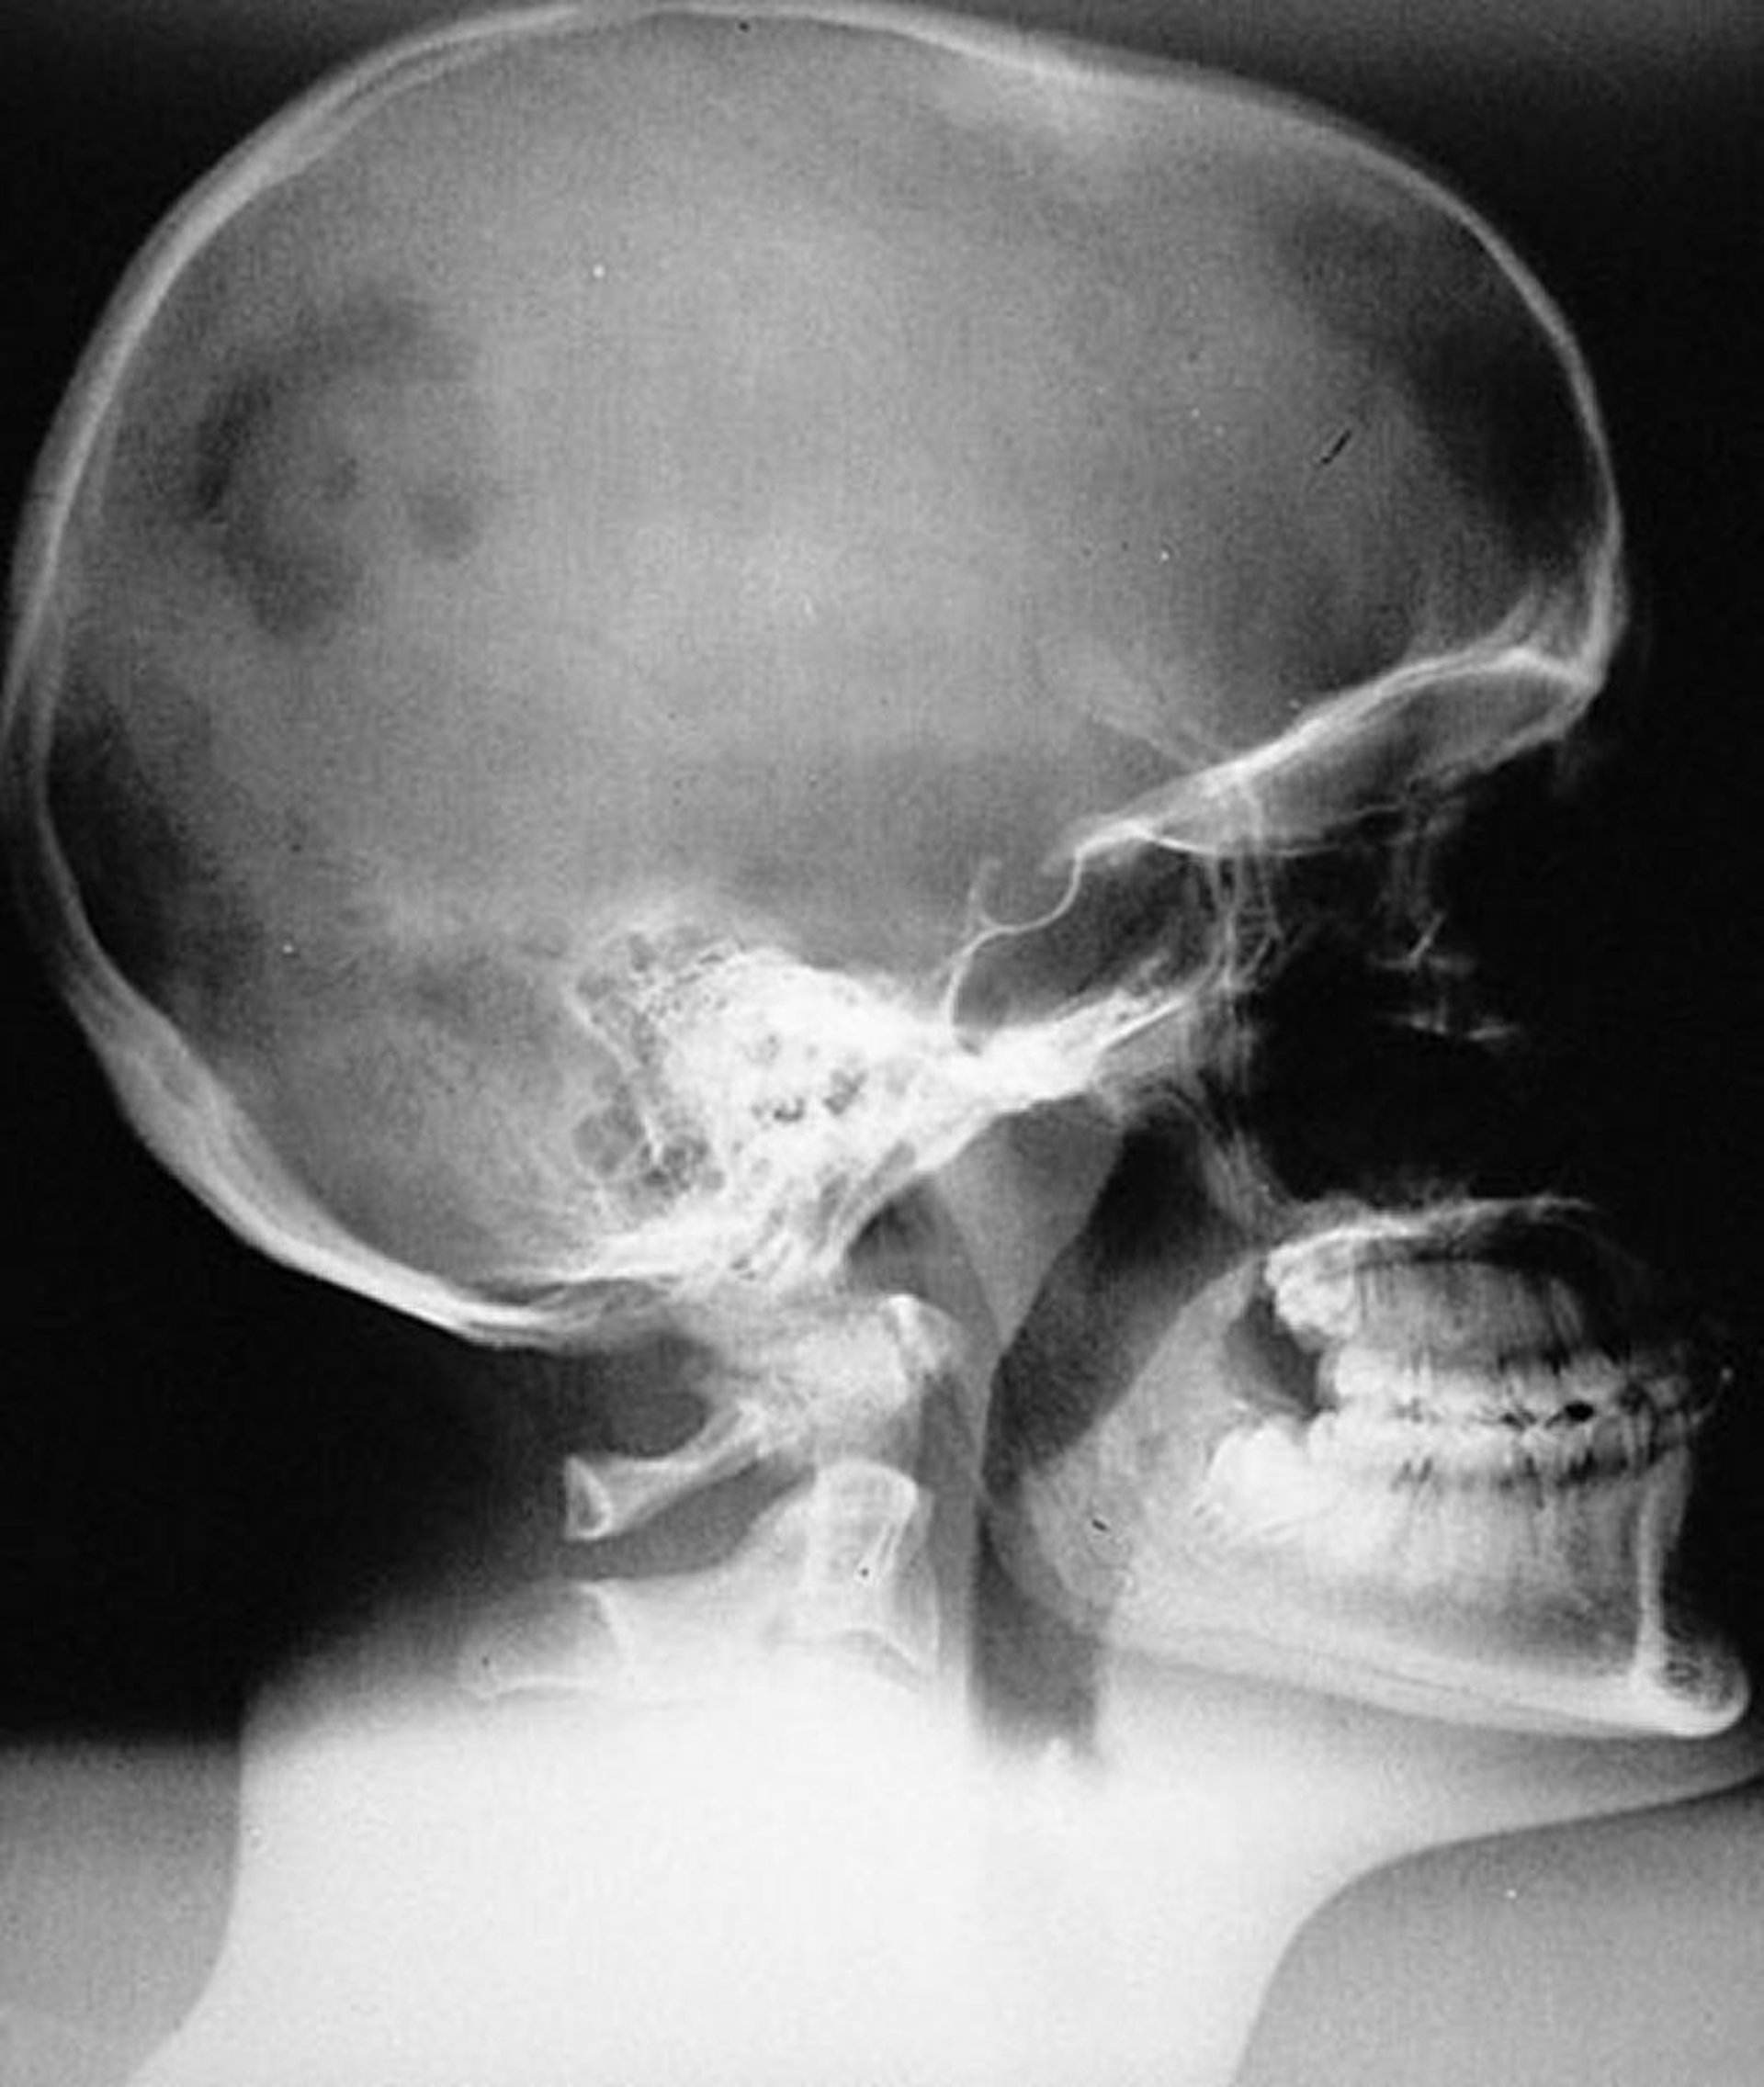

症状があるため,X線検査を実施することが多い。通常の骨病変は,境界が明瞭な円形または楕円形で,端部が傾斜して奥行きがあるように見える。ただし,X線像では,ユーイング肉腫,骨肉腫,その他の良性および悪性疾患,または骨髄炎と区別できない病変もある。

胸部X線を含む全身骨X線検査